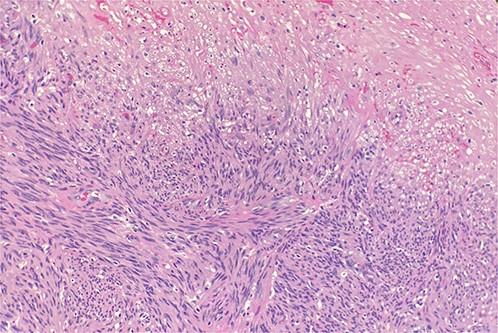

A 70-year-old male patient with a history of prostatic adenocarcinoma presented with testicular swelling. Testicular ultrasound revealed a 4 cm hypoechoic mass at the level of the epididymis. The patient underwent a radical orchiectomy. Pathology demonstrated a 4 cm mass located around the epididymis that was composed of elongated spindle cells arranged in intersecting fascicles. The tumor cells were found to have cigar-shaped nuclei and fibrillary eosinophilic cytoplasm (Fig. 1). Most of the lesions indicated relatively monomorphic cytology. Scattered moderate-to-focally marked nuclear pleomorphism was present. Focal necrosis was present, which may be suggestive of more aggressive biologic behavior. Ki 67% was approximately 10% and the mitotic activity was 7 mitotic figures per 10 high power-fields. The tumor margins were negative, with no invasion of the testicular parenchyma or spermatic cord. Immunohistochemistry showed strong reactivity with desmin and smooth muscle actin (Fig. 2). Overall, findings were diagnostic of low-grade leiomyosarcoma.

Microscopic examination reveals intersecting fascicles of monotonous spindle cells with indistinct borders, eosinophilic cytoplasm and cigar-shaped nuclei. There is necrosis on the right upper portion. Hematoxylin and Eosin 20×.